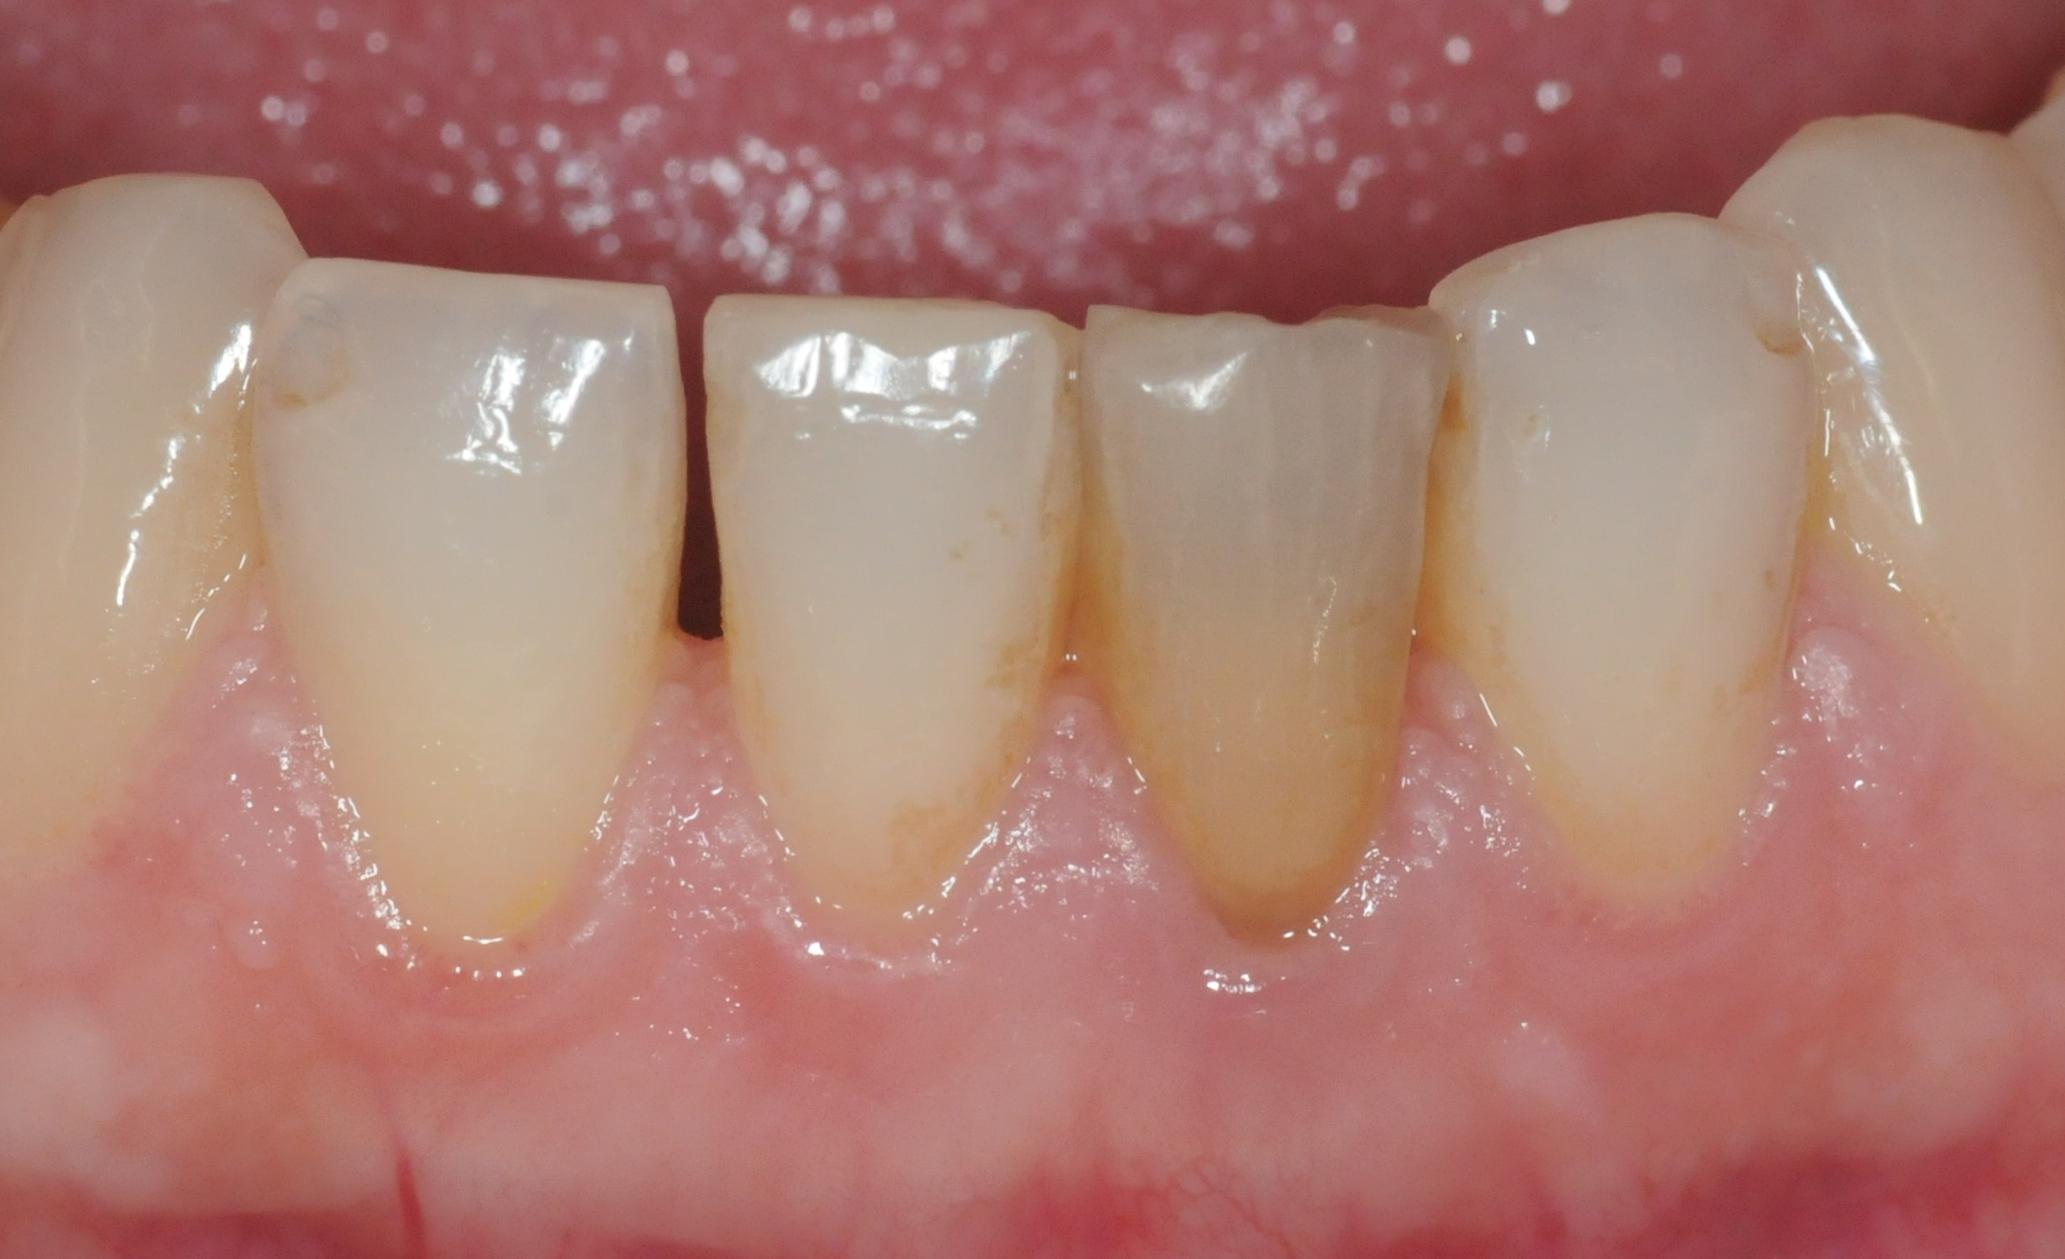

Wurzelbehandelte Zähne können dunkel werden, weil sich Farbstoffe im Zahn einlagern.

Wir haben die Möglichkeit, diesen von innen heraus zu bleichen.

Das Bleichmittel enthält Natriumperborat, das nicht mit der Schleimhaut in Berührung kommen soll. Es wird für ca. eine Woche in den Zahn eingebracht, der solange provisorisch verschlossen wird. Danach wird der Zahn mit einem Füllungskunststoff versorgt. Uns sind bisher keine nachteiligen Reaktionen bekannt geworden.

Ein Zahn wird ja von innen gebleicht, nachdem er Wurzelbehandelt wurde. Somit hat der Zahn natürlich schon eine gewisse strukturelle Schwächung erfahren. Es besteht also das Risiko, dass der Zahn bricht. Das wichtigste ist, dass der Zahnarzt den Zahn durch Ausbohren nicht noch weiter schwächt. Dies würde das Risiko erhöhen.

Zustand nach einer Woche Bleicheinlage. Der Zahn kann nun mit einer definitiven Füllung versorgt werden.